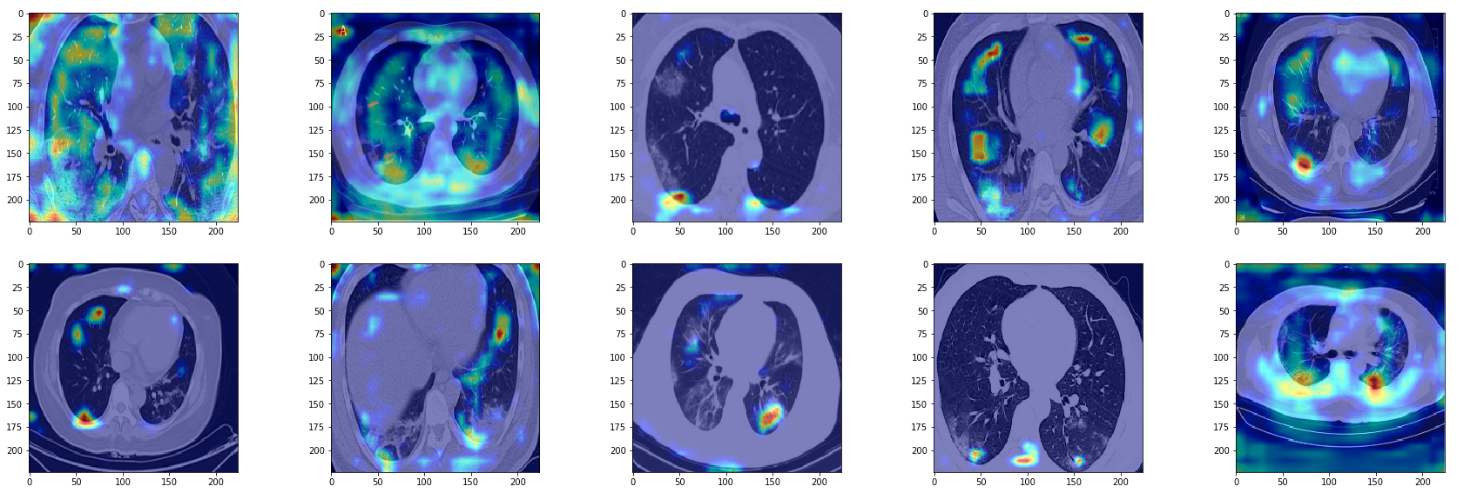

Let us now use the grad cam functionality to visualize a few examples from True positives, True negatives, False positives and False negatives.

True Positives

We see the model is able to focus on the ground-glass deformities that are characteristic of CT scans of COVID-infected patients. However, we also see that at times the network focuses on the boundary of the lung (in gray color) to make the decision. I am no radiologist to say whether we should be looking at the boundary to make the decision, but if not, then this is something that merits further inspection.

False Positives

In these examples, we see that the network focuses again on opacities but it isn't quite efficient enough to identify opacities corresponding to non-COVID pneumonia from COVID pneumonia.

True Negatives

In true negatives, the network seems to be focusing more on the lung boundary rather than the opacities in the lung. The opacities it sees are not very dense, or ground-glass like. Again, since I'm no radiologist I may be totally off track, but it seems as if the model depends on scarcity of opacities to make the negative prediction.

False Negatives

At last, in false negatives, the network is able to pick up on opacities but classifies them as negative. It seems as if the network has some threshold for opacities. In this case, it seems as if the network is thinking of them of as non-COVID pneumonia. In particular, for the images in row 2, col 2 and row 1, col 3, the network has hardly anything to work with.

Another artifact we see is the network focusing on edges of the image, which might be due to overfitting.